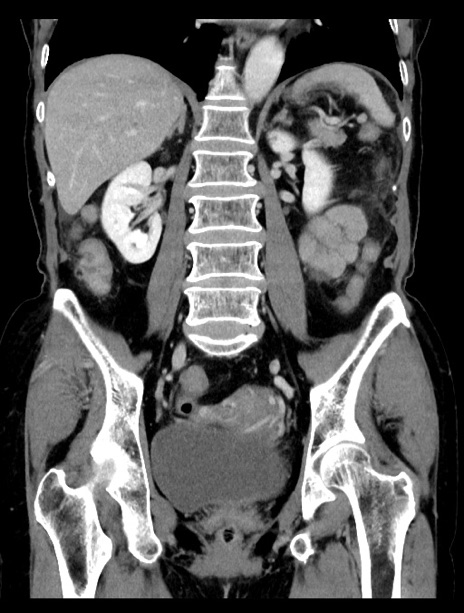

症例23(冠状断像)

【症例】70歳代女性

【主訴】下腹部痛・嘔吐

【現病歴】2日前より腹痛あり。昨日嘔吐あり。症状改善しないため来院。

【既往歴】胃GISTに対して胃部分切除後。

【身体所見】BT 37.1℃、BP 128/77mmHg、腹部:平坦・軟、下腹部に圧痛あり。

【データ】WBC 10200、CRP 0.31